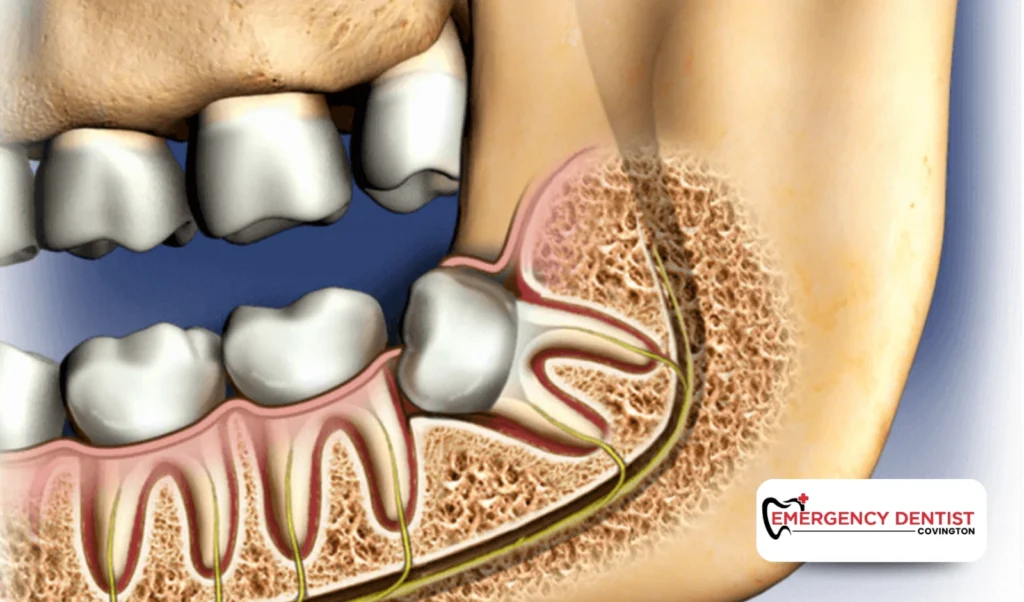

A surgical extraction is necessary when the tooth is partially erupted, broken, or located beneath the gums. This is common with an impacted wisdom tooth.

Surgical extraction may involve:

- Gently lifting gum tissue

- Removing small sections of bone

- Dividing the tooth into smaller pieces

Since this is a more advanced dental procedure, wisdom teeth removal cost is typically higher than with a simple extraction.

How an Impacted Wisdom Tooth Affects Cost

An impacted wisdom tooth does not fully come through the gums. It may grow sideways or push against neighboring teeth. These situations often require oral surgery.

Because additional time, precision, and planning are involved, impacted cases usually increase the average cost of a wisdom tooth removal. When patients ask, how much does a wisdom tooth extraction cost, the answer often depends on whether the tooth is impacted or fully erupted.